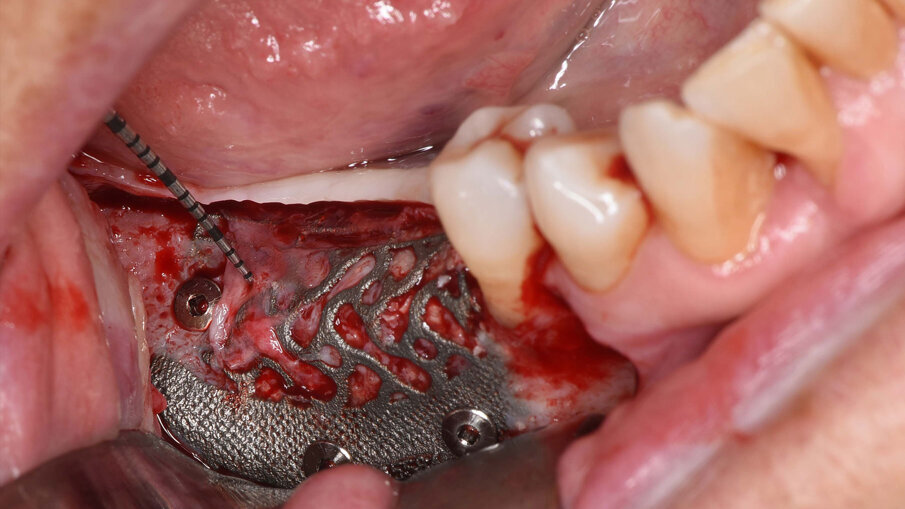

Il prelievo di osso autologo particolato è stato eseguito dal ramo mandibolare, distalmente alla zona da ricostruire mediante uno scraper (SafeScraper Twist, META). La griglia è stata provata nel sito ricevente per verificarne la congruità. Ogni residuo di tessuto connettivo è stato rimosso; per aumentare la rivascolarizzazione precoce del materiale innestato, sono state eseguite delle perforazioni della corticale ossea del sito ricevente (Figg. 3, 4). Dopo preparazione dei siti implantari, sono stati posizionati due impianti “root form” e “bone level” in zona 4.6 e 4.7 (4.1 x 8 mm; Straumann) usando una dima chirurgica. La griglia è stata quindi riempita con un mix di osso autologo ed eterologo (Geistlich Bio-Oss, Gestlich Pharma) in rapporto 1:1, è stata fissata con 3 micro-viti in titanio di 1.4 mm di diametro (MC Bio) ed è stata ricoperta con una membrana riassorbibile (Geistlich Bio-Gide, Gestlich Pharma; Figg. 5, 6). La sutura è stata eseguita per prima intenzione (Fig. 7).

Fig. 5_Visione intra-operatoria della griglia riempita con un mix di osso autologo particolato prelevato dal ramo mandibolare e osso eterologo in rapporto 1:1 e fissata mediante 3 viti in titanio di 1.4 mm di diametro e dopo inserimento di due impianti osteointegrati.

Fig. 6_Visione intra-operatoria della membrana riassorbibile (Geistlich Bio-Gide) posizionata sopra la griglia.

La paziente è stata dimessa con istruzioni dietetiche e terapia antibiotica, antisettica e antiedemigena associata alla terapia antidolorifica, al bisogno. Subito dopo l’intervento è stata eseguita una CBCT di controllo per verificare l’incremento ottenuto (Figg. 8a, 8b). Le suture sono state rimosse 20 giorni dopo e la paziente è stata sottoposta a controlli clinici a 1-3-6 mesi dall’intervento che non hanno evidenziato alcuna complicanza. Al sesto mese, si è proceduto alla rimozione della griglia e alla scopertura degli impianti (Figg. 9a-10). Al momento della rimozione della griglia, non è stata visibile alcuna significativa perdita ossea al di sotto della griglia e il tessuto osseo rigenerato è apparso di notevole consistenza. La morfologia della griglia, in parte occlusiva, ha dimostrato una maggiore facilità della sua rimozione rispetto a griglie non occlusive.

Figg. 9a-9c_Foto intra-operatoria durante la rimozione della griglia in titanio che evidenzia l’incremento osseo ottenuto e l’assenza di perdita ossea al di sotto della griglia.

Fig. 10_Foto clinica che mostra la scopertura dei due impianti nel tessuto rigenerato, eseguita nella seduta di rimozione della griglia.